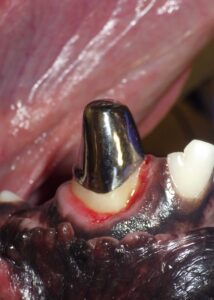

A root canal in pets is a dental procedure that removes the damaged pulp (inner tissue) of a tooth, disinfects the space, and seals it with a safe filling material. The goal is to retain the tooth’s structure and function while eliminating pain and infection.

What to Expect During and After a Pet Root Canal

Why a Board-Certified Veterinary Dentist Matters